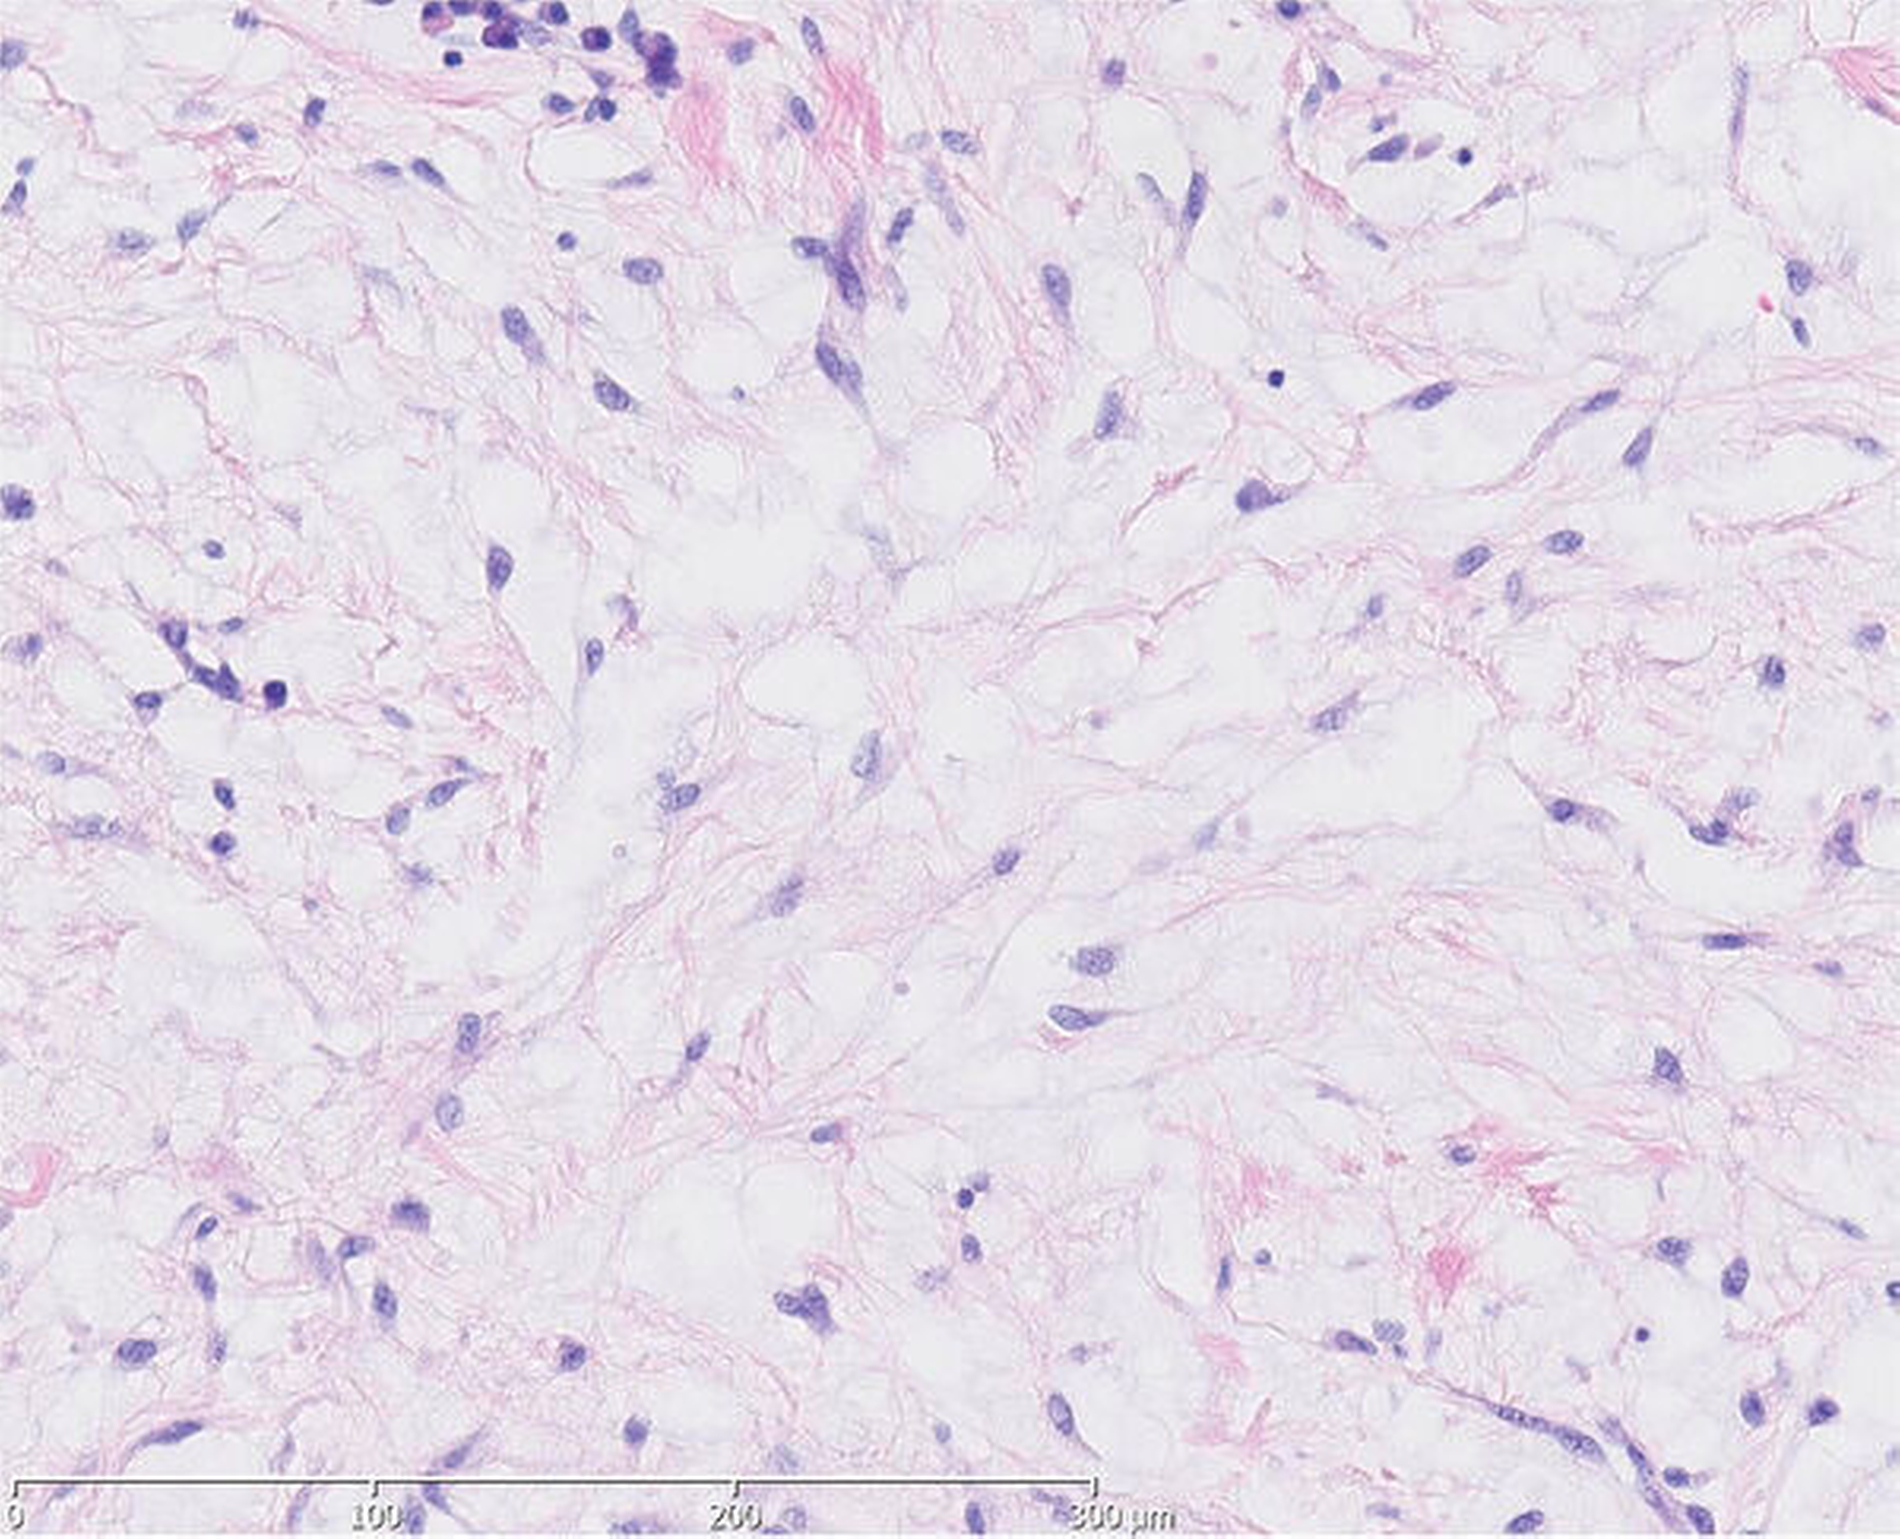

In der histopathologischen Aufbereitung zeigte sich in den weichgewebigen Resektaten eine interstitielle myxoide Matrix mit spindeligen Zellen mit geringen Kerngrößenschwankungen. Zur weiteren Befundeinordnung erfolgte eine immunhistochemische Aufbereitung. Dabei waren Anteile eines Myxofibroms mit fokal chronisch-erosiven Entzündungen im Bereich der Oberfläche sowie eine Hyperplasie des Plattenepithels erkennbar.

Um Aussagen zur intraossären Ausbreitung sowie zur Dignität des nachgewiesenen Myxofibroms treffen zu können, wurde das Material weiter aufbereitet. In der Alcian-PAS-Färbung zeigten sich keine infiltrativen Anteile des beschriebenen Myxofibroms sowie keine Destruktion des Knochengewebes. Es gab keine Anzeichen für Malignität.